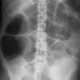

En cuanto al diagnóstico por imágenes, la radiografía simple de abdomen se utiliza frecuentemente como una primera aproximación para evaluar la presencia de distensión abdominal y otros signos característicos de la alteración motora del intestino. En una radiografía simple del abdomen, se pueden observar la distensión de los lazos intestinales tanto del intestino delgado como del grueso, los cuales se llenan de gas debido a la falta de movimiento peristáltico normal que permite el paso de los contenidos intestinales. Este fenómeno provoca la acumulación de aire en los lazos intestinales, lo que se traduce en la aparición de la distensión observada en las imágenes. Además, es posible que se observen niveles de aire-líquido en ciertas áreas del intestino, lo que indica la presencia de un trastorno en el flujo normal de los contenidos intestinales, aunque sin una obstrucción mecánica clara.

Sin embargo, en algunos casos, puede resultar difícil diferenciar entre el íleo y una obstrucción parcial del intestino delgado, ya que ambas condiciones pueden mostrar signos similares en las imágenes radiográficas, como la distensión de los lazos intestinales y la presencia de niveles de aire-líquido. En este contexto, una tomografía computarizada (tomografía axial computarizada o TAC) del abdomen puede ser particularmente útil. La tomografía computarizada ofrece una visión más detallada de las estructuras abdominales y puede ayudar a identificar signos de obstrucción mecánica, como la presencia de una masa, adherencias, hernias o cualquier otra causa anatómica que esté bloqueando el paso del contenido intestinal. La tomografía computarizada es especialmente valiosa en pacientes postoperatorios, donde la distensión abdominal podría ser confundida con signos de obstrucción parcial debido a adherencias o cambios postquirúrgicos en los intestinos. En tales casos, la tomografía computarizada permite confirmar o descartar la presencia de una obstrucción intestinal mecánica, lo que es crucial para determinar el tratamiento adecuado.